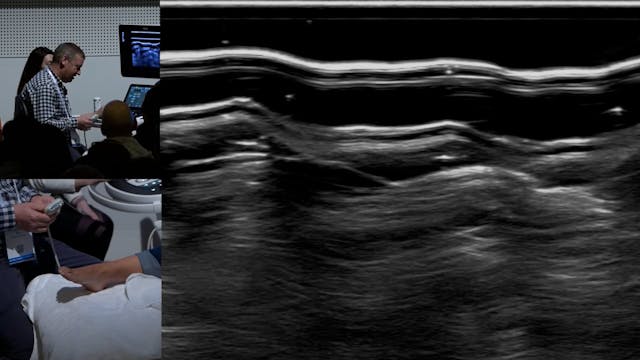

Ganglia in unusual places

MSK • 27m